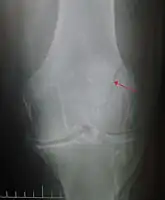

Differential diagnosis

Some people have a normal two-part patella which can appear as a fracture. The fragment is usually seen in the top outer corner of the patella and can be distinguished from a fracture by being present in both knees.[6]